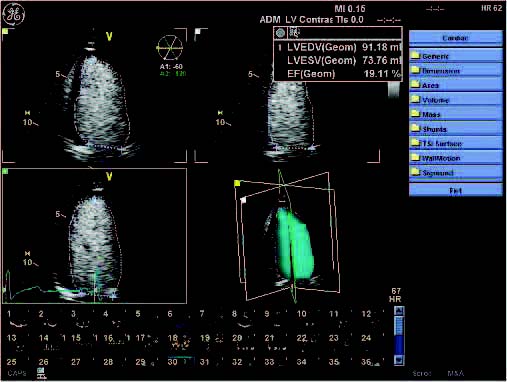

GE Vivid 7 Imaging Modes

- B-Mode

GE Vivid 7 Features:

- Analysis program